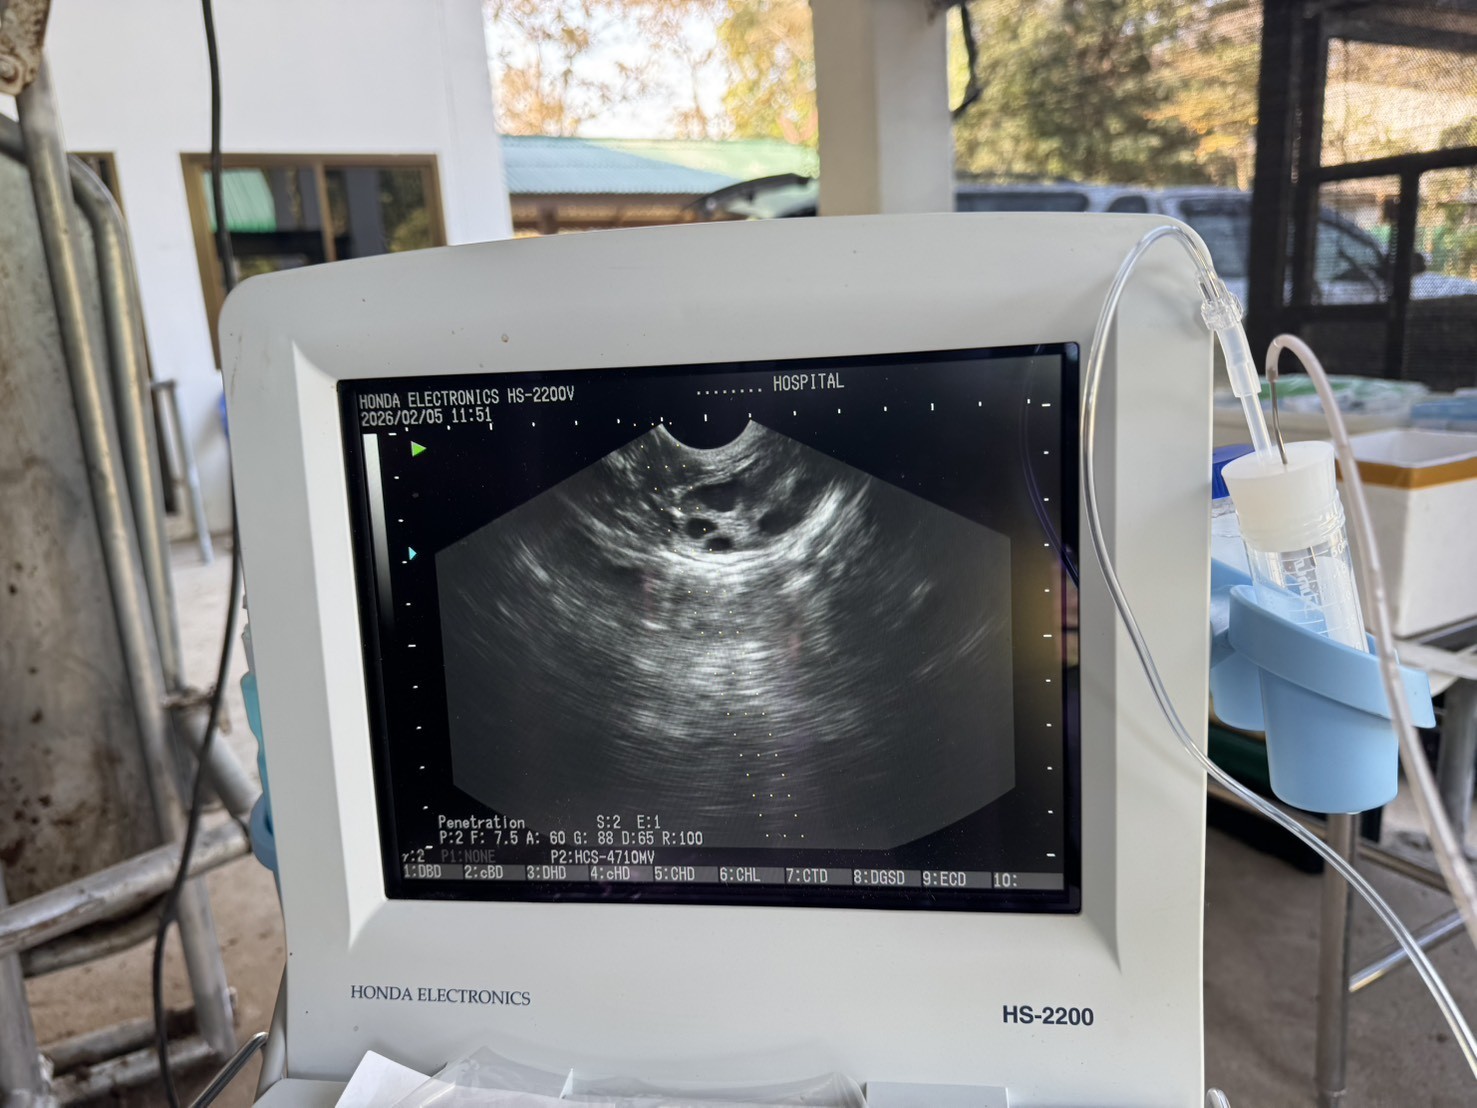

วันที่ 5 กุมภาพันธ์ 2569 ศูนย์วิจัยการผสมเทียมและเทคโนโลยีชีวภาพเชียงใหม่ ปฏิบัติงานเจาะเก็บโอโอไซต์ จากแม่โคพันธุ์ไทยแบล๊ค DLD เพื่อใช้ในการผลิตตัวอ่อน แบบนอกร่างกาย (OPU-IVP) โครงการ การยกระดับศักยภาพการผลิตเนื้อโคขุนระดับพรีเมียม ด้วยโคพันธุ์ไทยแบล็คกรมปศุสัตว์ (ปีที่ 1)

1.ทำการเจาะเก็บโอโอไซต์ด้วยวิธี Ovum Pick-up (OPU) จากแม่โค จำนวน 12 ตัว

2. ทำการเพาะเลี้ยงโอโอไซต์ที่เจาะเก็บได้ เพื่อใช้ในกรปฏิสนธิแบบนอกร่างกาย (IVF) ในขั้นตอนต่อไป